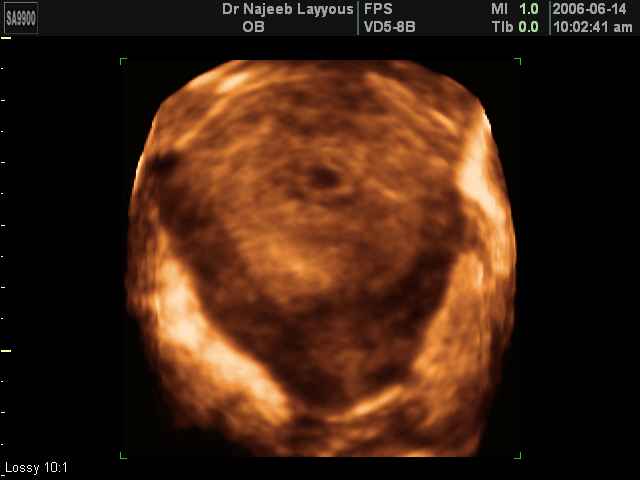

3D First Trimester Ultrasound Scan Photos